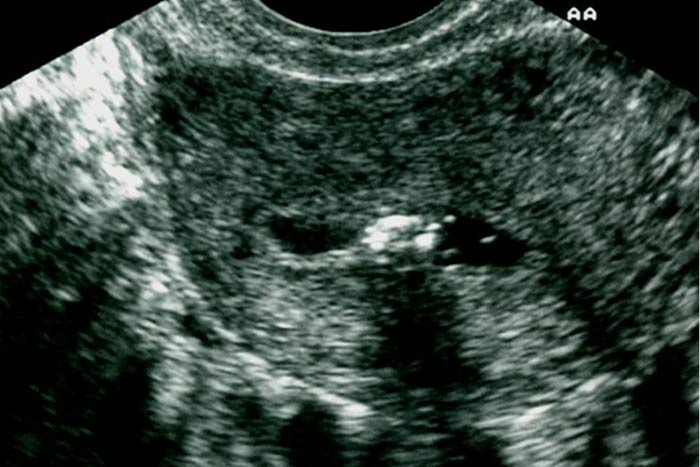

تخریب لایه بازال آندومتر بدنبال کورتاژ خشن و حاملگی پیشرفته و یا ابتلا به سل منجر به ایجاد اسکار و تشکیل باند فیبروتیک در داخل کاویته رحمی می شود. هیستروسونوگرافی به همراه روش سه بعدی 3D

مزایای زیادی در تشخیص چسبندگیها دارد تعیین محل دقیق چسبندگی در ارزیابی قبل از عمل جراحی از اهمیت زیادی برخوردار است. (1) چسبندگی معمولا بشکل باندهای فیبروتیک نازک و اکوژن که در عرض کاویته رحم کشیده شده اند، رویت می شود. نمای پاپیون شکل (bow-tie)در هیستروسونوگرافی نیز مشخصه چسبندگی داخل رحمی است. (7) .